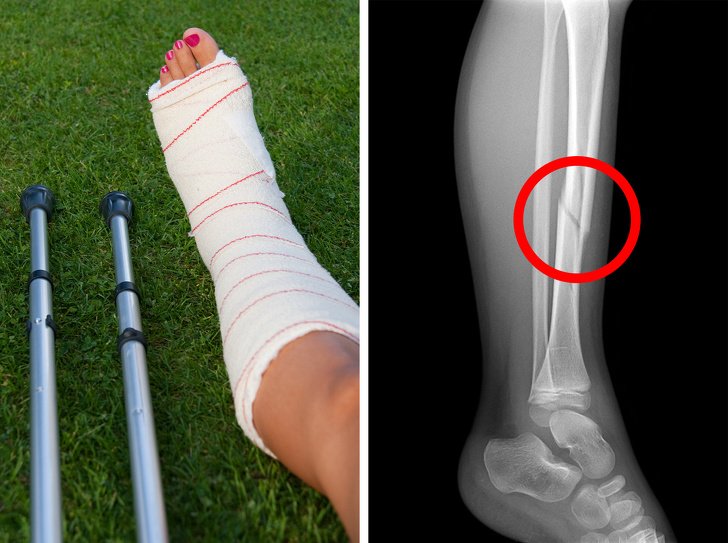

• Probleme me kockat

Kalciumi është thelbësor për zhvillimin e kockave dhe shëndetin e kockave, veçanërisht gjatë fëmijërisë. Sidoqoftë, të gjitha produktet e qumështit – si proteina shtazore në përgjithësi – janë acid, gjë që zvogëlon marrjen e kalciumit. Një studim sugjeron që gratë që pinë 3 ose më shumë gota qumësht në ditë kanë rrezik më të madh të frakturave.